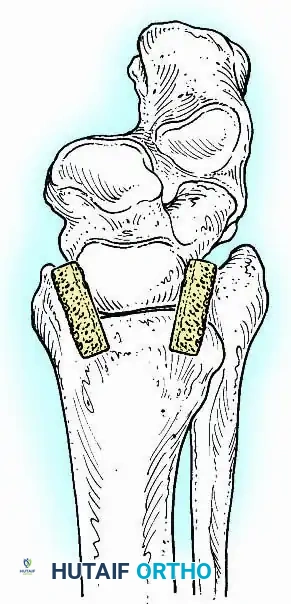

Transmalleolar (Transfibular) Approach

This approach utilizes a lateral incision over the distal fibula. A transfibular osteotomy is performed, reflecting the distal fibula distally or excising it entirely to be used as autograft. This provides unparalleled exposure of the lateral half of the joint and the posterior facet. It is highly effective for correcting severe varus/valgus deformities. A supplementary medial incision (medial malleolar osteotomy) can be added for complete joint exposure.

- Contour Preservation (Fishscaling): The remaining articular cartilage is meticulously denuded using curettes, and the subchondral bone is "fishscaled" or aggressively petalled with a sharp osteotome. This preserves the native ball-and-socket contour of the ankle, maximizing inherent bony stability and minimizing limb shortening.

- Planar Resection (Parallel Cuts): Two parallel cuts are made—one through the distal tibial plafond and one through the talar dome—using an oscillating saw. This technique resects a minimal amount of bone but creates perfectly flat, highly vascular cancellous surfaces that allow for excellent apposition and easy posterior translation of the talus. Extramedullary alignment guides (often repurposed from total knee arthroplasty systems) can be utilized to ensure precise, parallel resections.